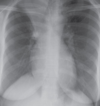

Rx normal.

Radiografía anteroposterior.